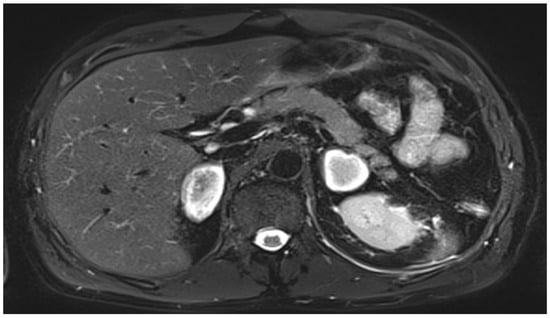

2. Case